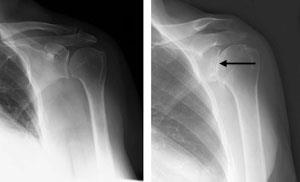

(Left) An x-ray of a healthy shoulder joint ,(Right)Osteoarthritis of the shoulder.

Note the decreased joint space (arrow).